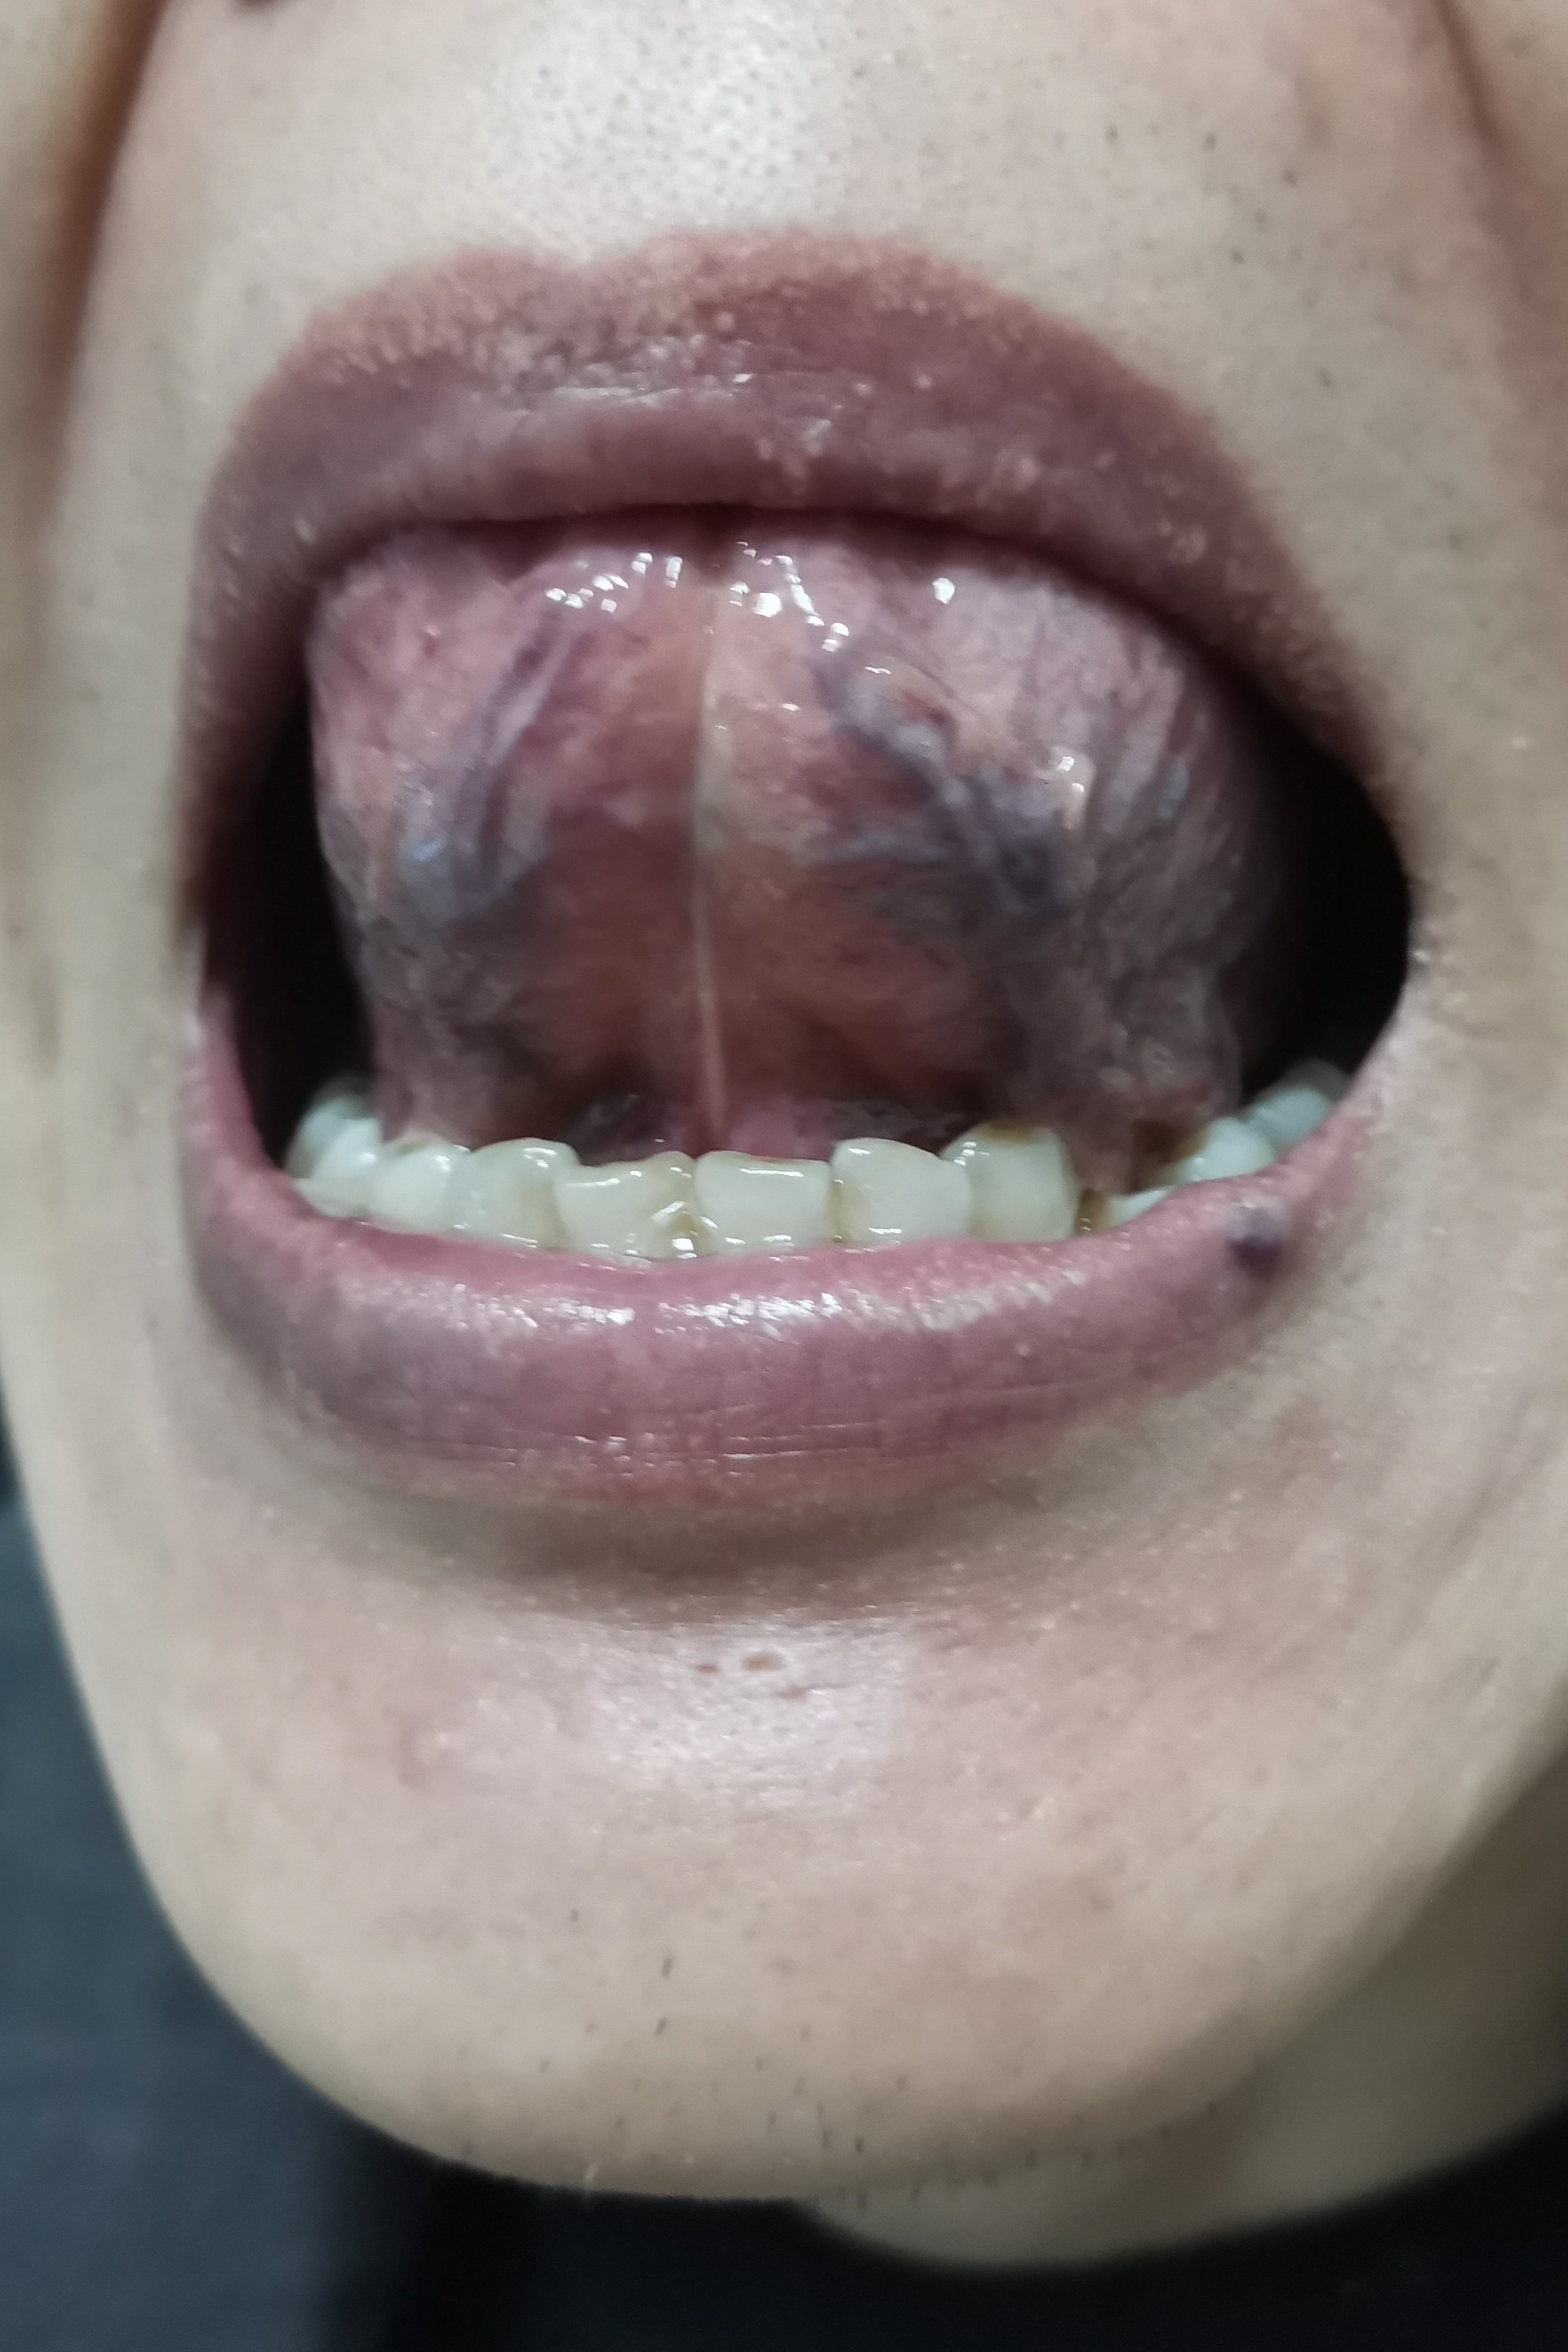

左侧臀部痒消失,新冠后遗咳嗽基本消失,小便分叉有减轻9成,小便色黄味重减轻,阴茎阴囊潮湿减轻,肛周瘙痒减轻,肠鸣减轻,腰酸减轻,余症仍在:头面发油、发少,大便有时后段烂、味重、体力差、精神状态差、心情低落、多梦,脉弦细,舌淡胖齿痕,苔薄黄,舌下*曲,甲状腺结节、轻微脂肪肝、双肾泥沙型结石及胆管结石,左膝关节弹响,跑步时快就会疼,右肩袖轻微撕裂后遗外展受限,应为肌肉黏连,后脑勺接近项部左侧有被皮肤科大夫诊为神经性皮炎的边界清晰的红色凸起痒,视力有点模糊,手脚稍凉,有牙龈萎缩,早泄时好时坏将近10年。